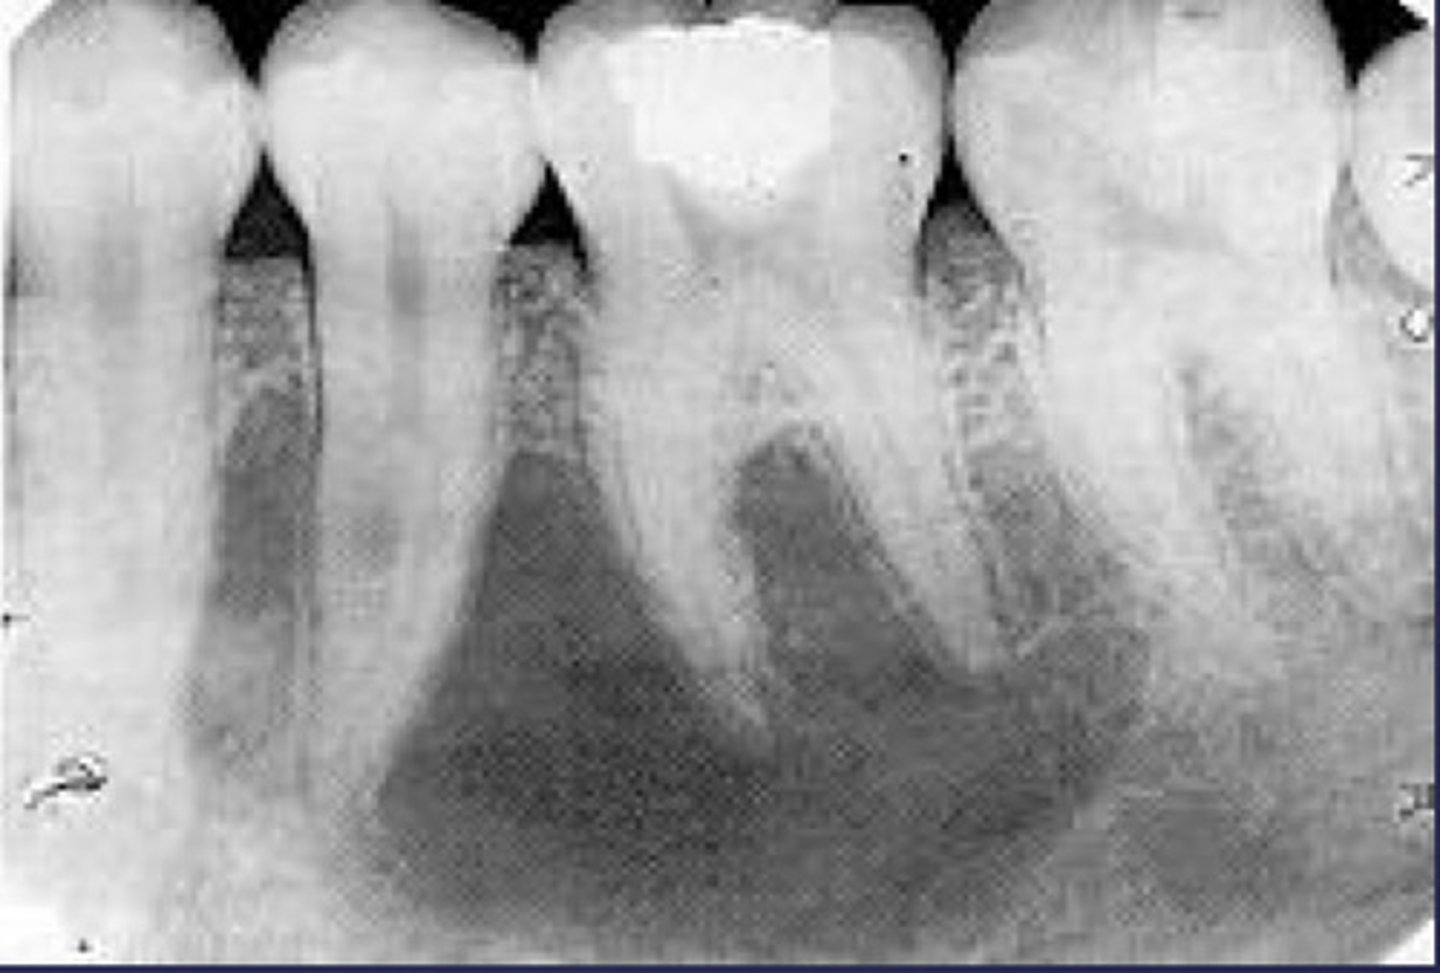

how would you describe this lesion? (not the giant cavity btw)

A. defined, corticated, periapical radiolucency causing loss of lamina dura and PDL space on #6-7

B. defined, non-corticated, periapical radiolucency causing loss of lamina dura and PDL space on #6-7

C. ill-defined, circular radiolucency located above tooth #7

D. well-defined, corticated, radiopacity

- Also note epicenter located above apex # 7 which has large dental caries.

What category would this lesion be part of?

Inflammation/benign

all of the following could be a differential diagnosis for the following lesion EXCEPT?

A. radicular cyst

B. Periapical granuloma

C. apical rarefying osteitis

D. renal osteodystrophy

what category would this lesion be classified into?

inflammatory/benign cystic